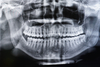

Radiographie numérique au cabinet dentaire du Docteur Benjamin Knaebel, à Chasselay (69380)

Quand la radiographie est-elle nécessaire ?

Elle est souvent utilisée pour :

• Détecter des caries invisibles à l’œil nu

• Évaluer l’état de l’os avant une pose d’implant

• Préparer un traitement orthodontique

• Suivre l’évolution d’un traitement de racine (endodontie)

• Observer la position des dents de sagesse

• Vérifier l’état des prothèses ou restaurations

Les avantages de la radiographie numérique